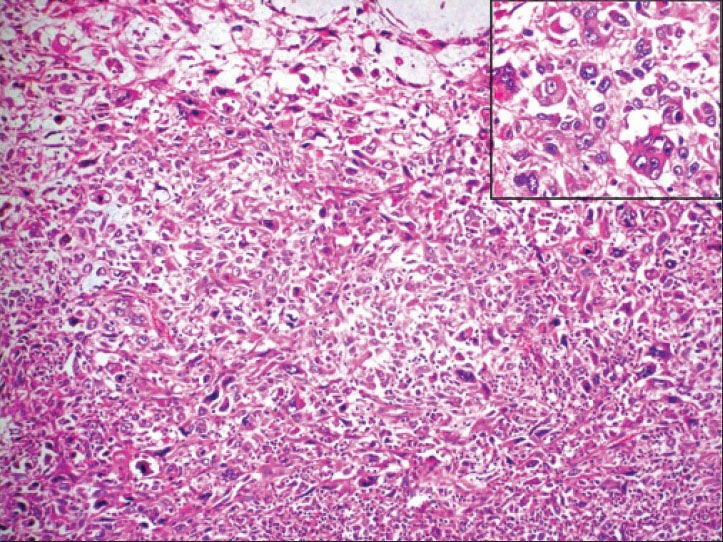

Microscopy revealed a pleomorphic malignant tumor comprised of both epithelial and mesenchymal elements. The cells were arranged in sheets, nests, and cords. Binucleated and multinucleated tumor cells were evident. Few tumor cells had abundant granular eosinophilic cytoplasm. Many abnormal mitotic figures were also noted [Figure 2]. The tumor cells were infiltrating up to the overlying skin Three of the nine axillary lymph nodes showed tumor deposits. Immunohistochemistry showed that the tumor cells were reactive for vimentin [Figure 3], desmin, and cytokeratin; and were negative for estrogen receptor (ER), progesterone receptor (PR), and Her-2/neu. Based on the above features, the tumor was diagnosed as metaplastic carcinoma with rhabdomyosarcomatous element.

| Figure 3:Axial fused PET/CT images show FDG avid metastatic lesions in brain (a – arrow), left iliac marrow (b – arrow), D12Tumor cells showing strong cytoplasmic positivity for vimentin (×400)